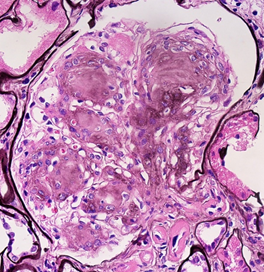

Mikroskopický nález:

• Expanse extracelularní matrix (diabetická glomerulosklerosa)

• Ztluštění bazálních membrán

• Vaskulární změny

• 1+2+3: ischemie

• Poškození glů: Proteinurie/Nefroticky syndrom

• DM glomerulosklerosa:

• Kimmelstiel-Wilson= difusní a nodulární glomerulosklerosa

• Proteinurie a progresivní selhání ledvin